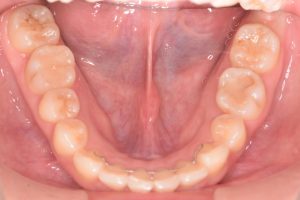

下あご

0000000012

0000000140